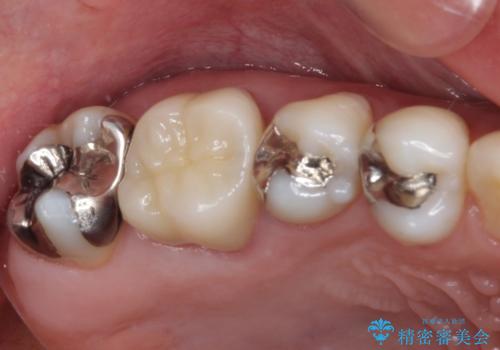

痛む奥歯 セラミッククラウンによるむし歯治療